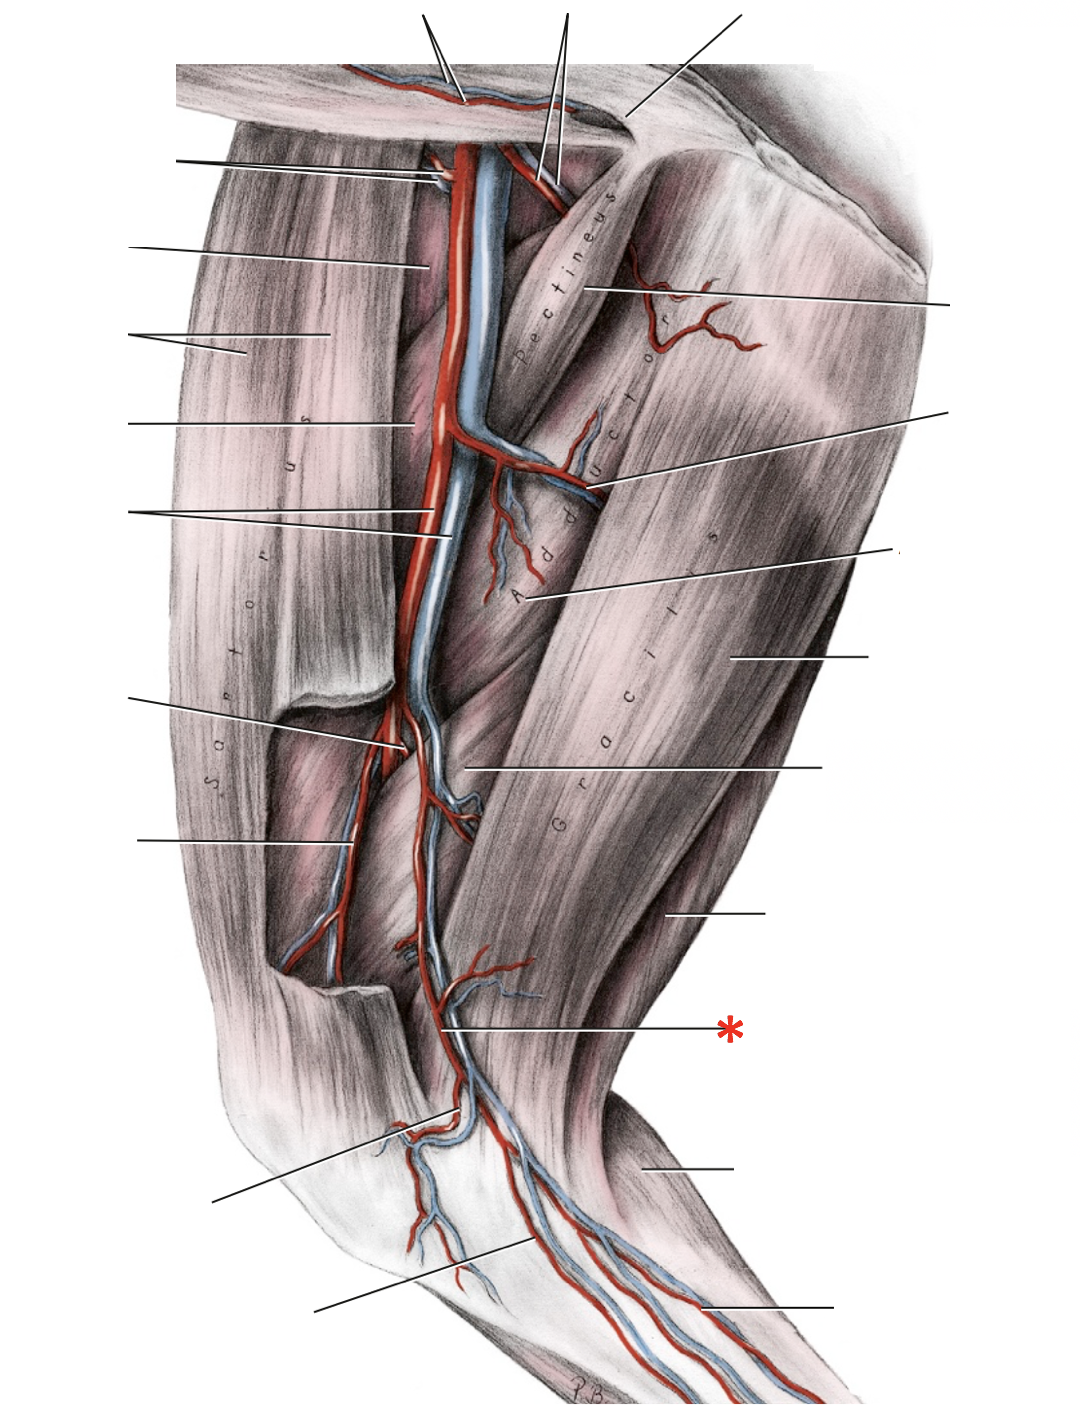

N. tibialis

A. saphena r. caudalis

A. saphena

A. saphena

A./v. saphena

V. saphena medialis

V. saphena lateralis

V. saphena lateralis r. caudalis

V. saphena lateralis

V. tibialis caudalis

- ex. v. poplitea ex v. femoralis